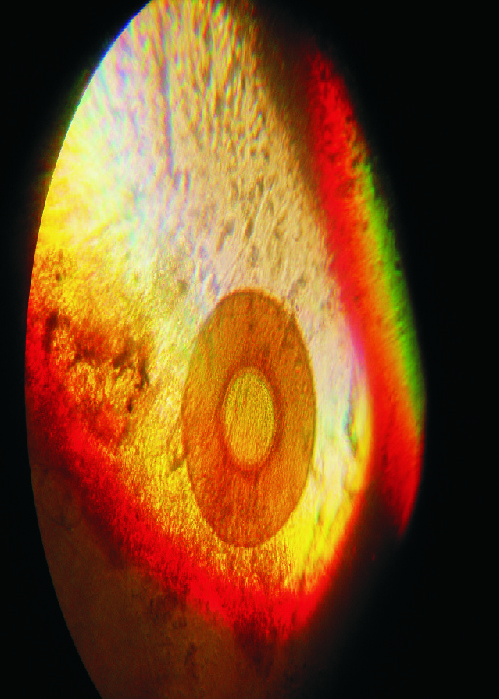

znalezione w odchodach - powiekszenie x120 i x500

(jest okragle, tylko na tych zdjeciach robi sie jajo)

Teraz o tym co (słabo

) widać. Na nr.1 to może być skorupka pełzaka - ameby. Na drugim - nie wiem (wydaje mi się zbyt symetryczny ten obiekt, żeby mógł być czymś, co nas może interesować

). Teoretycznie mógłby być niby jakąś cystą, niekoniecznie groźną, ale moim zdaniem jest zbyt symetryczny.

to sa fotki tego samego ustrojstwa w powiekszeniach x120 i x500,